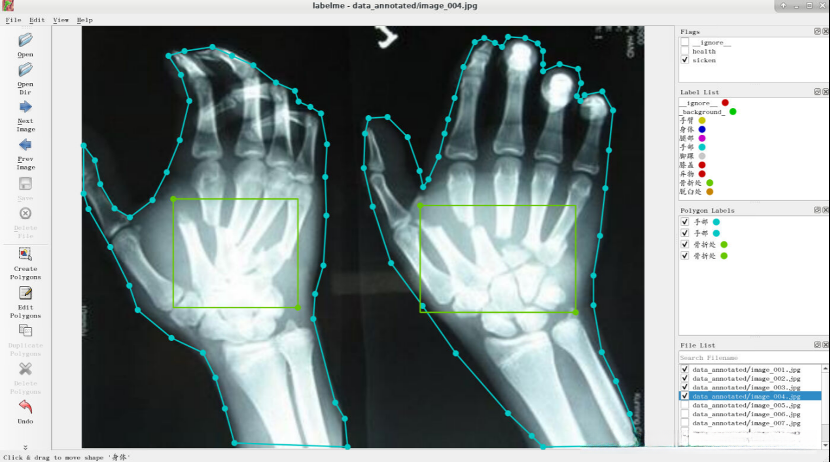

由于结果图片过多,仅展示部分图片。

任务实施过程

- 使用labelme进行图像标注

观察图像,判断患者是否健康,认为该患者是健康的,所以flag选择“health”。

请在电子图像中识别出人体关键部位,并通过右键点击执行"Create Polygons"操作。

左键点击图片,将图像中的手臂标注出来,选择相应的label,然后点击OK。

点击OK后,结果如下图所示。

10.点击“Next Image”,将图像中人是否是健康的,无法判定时选择“ignore ”。

将图像中人体标注出来并选择相应的label。

点击“Next Image”,判断健康状况并选择相应的flag。